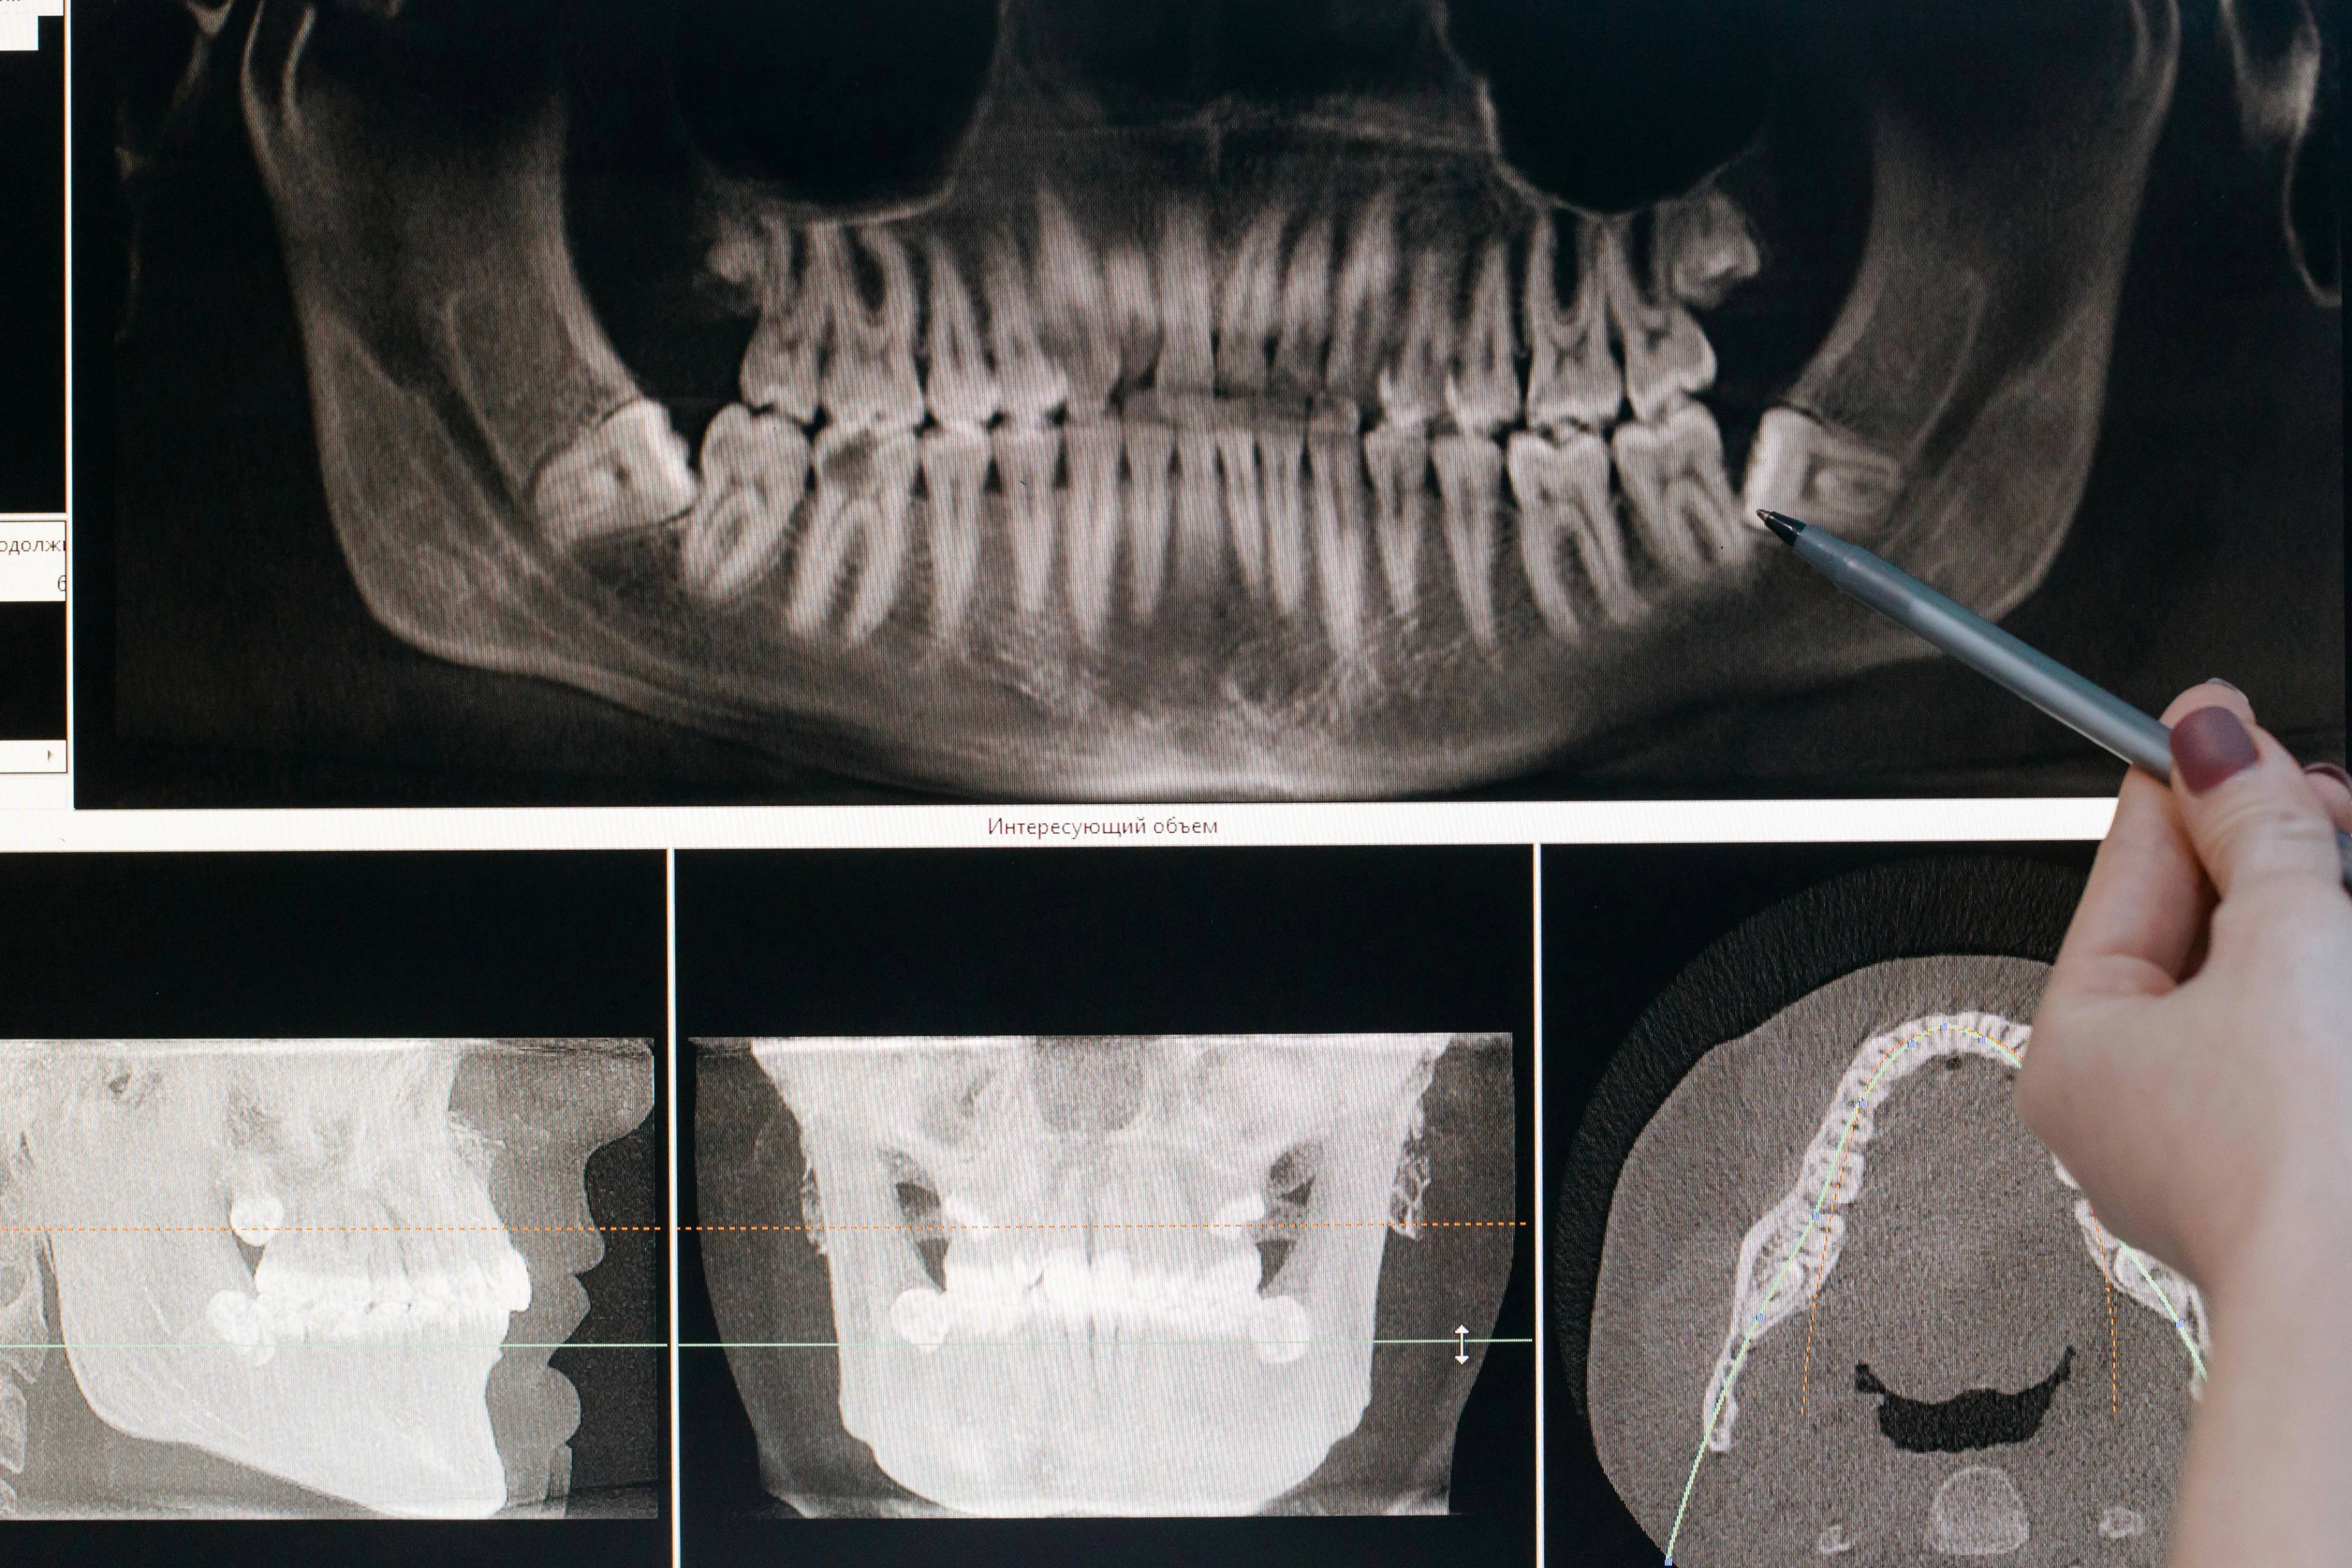

Impacted tooth extractions

Extracting hidden teeth relieves pain and helps align your smile beautifully